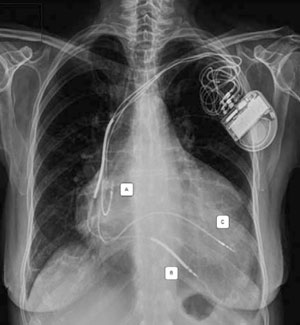

Recientemente se han publicado estudios utilizando la alternativa de la estimulación del VI por vía endocárdica, lo que puede realizarse por diferentes técnicas40), (41(Figura 4). Incluso se ha logrado la estimulación endocárdica sin electrodo (leadless) a través de un dispositivo que se implanta a nivel endocárdico del VI y estimula mediante ultrasonido transmitido desde un dispositivo subcutáneo enfrentado42.

Figura 4: Radiografía de tórax de un paciente a quien se le implantó un TRC-D por vía endocárdica transeptal usando la técnica Jurdham. A. Electrodo auricular. B. Electrodo ventricular con doble bobina de desfibrilación. C. Electrodo endocárdico en pared lateral del VI a través de septum interauricular. Gentileza del Dr. Benjamin Elencwajg.

La estimulación endocárdica tiene la ventaja de que la conducción desde el endocardio al epicardio (endo-epi) es más rápida que la inversa (epi-endo), por lo que se logran complejos QRS más finos y resincronización más fisiológica. Además, se puede elegir el sitio de estimulación con mayor precisión. La desventaja es la alta tasa de stroke y, por tanto, el paciente debe quedar anticoagulado con warfarina con objetivos similares a los usados para las válvulas mecánicas.